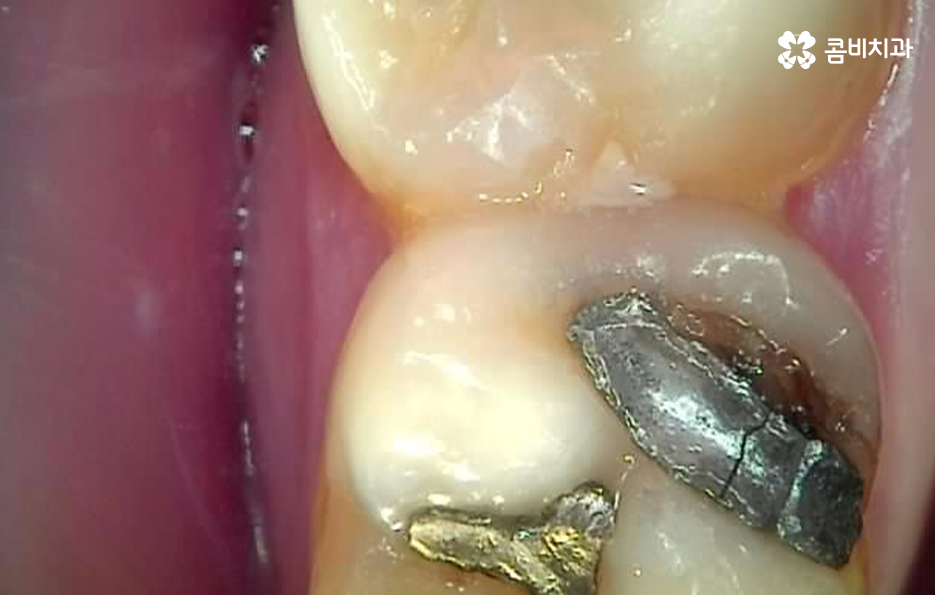

저작 기능에서 주된 역할도 하지만 위 사진을 다시 보시면 사랑니가 부분 매복되어 있는 상태로 누워서 자라고 있기 때문에 사랑니와 어금니 인접면에서 청결 관리가 잘 안되는 문제로 충치나 치주질환을 앓고 계신 분들도 많기 때문에 사랑니로 인해 어금니 문제가 발생하는 경우도 많이 있어요

다시 위 어금니 사진을 살펴보면 사랑니가 매복되어 있긴 하지만 위쪽 부분이 살짝 잇몸 밖으로 드러나 있는 것을 볼 수 있는데요. 평소 칫솔질을 잘하더라도 사랑니로 인해 청결관리에 미흡한 점이 생기면 주변 치아에도 충치가 전염되는 등의 안좋은 영향을 주는 경우가 많으며 부분 매복 사랑니의 경우 충치가 아니더라도 잇몸 염증의 주된 원인이 되고 있기 때문에 발치하는 것을 각종 구강질환을 예방하기 위해 권하고 있어요

오늘 소개드린 환자분의 케이스는 사랑니 만의 문제라고 보긴 어렵고 오래된 보철물로 인한 2차 충치로 볼 수 있으며 새로운 보철물로 어금니 충치치료 다시 해야하는 케이스로 볼 수 있는데요

중년 이후에는 단지 칫솔질이나 식습관이 좋지 않아서 충치가 발생되는 사례보다는 오래된 보철물과 사랑니 문제, 치아 사이의 미흡한 치석 관리 등이 복합적으로 치아 문제를 일으키는 경우가 더 많을 거예요